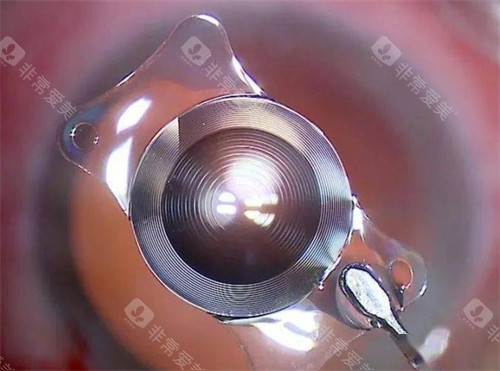

晶体选择是费用差异的核心来源,政策免费提供的为国产基础型单焦点晶体,满足基本视力好转需求。若申请者希望选择功能更优的晶体,需自付差价:

进口单焦点晶体:1400-12000元

高端功能性晶体(如三焦点、景深延长型晶体):15000-30000元起

晶体差价的设定,既确保了基本医疗需求,又为有更高视觉质量追求的患者提供了选择,避免了“一刀切”的僵化模式,兼顾公平与个性化需求。